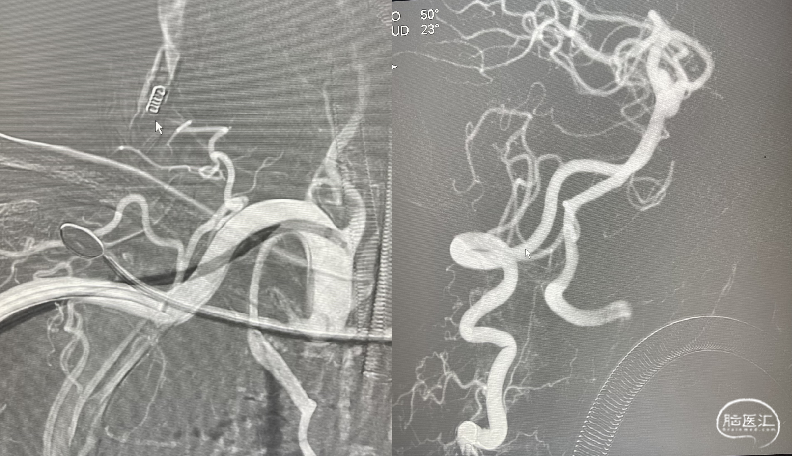

Fastrack支架导管顺中间导管在Traxcess微导丝导引下,顺利通过瘤体到达左侧大脑后动脉P3段,位置满意后撤出微导丝。

3

输送Tubridge®血流导向密网支架:支架导管逐渐后撤,支架头端部分送出支架导管,将头端锚定于基底动脉小脑上动脉开口下,逐渐缓慢释放支架,使支架充分打开,并顺利跨瘤颈到达动脉瘤流入道,完整释放支架。

释放支架:3.5mm*30mm Tubridge®血流导向密网支架缓慢释放,Tubridge®血流导向密网支架中点mark稳稳的定位在动脉瘤瘤颈处,蒙片显示支架位置良好,打开完全。

4

利用微导丝按摩支架。